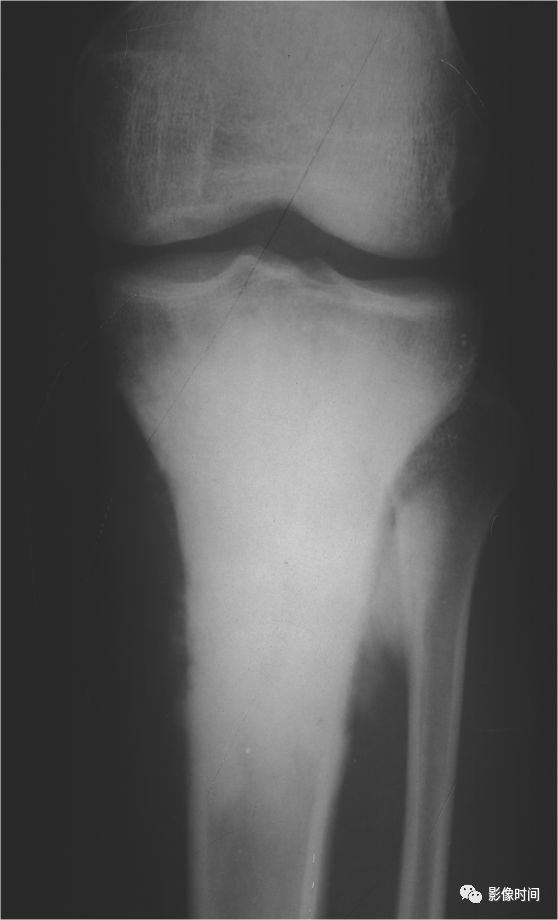

(四)压迫性骨质缺损   压迫性骨质缺损系因骨皮质局部受压,致使骨萎缩以致缺损、消失出现碟形的骨质缺损(图 12、图 13、图 14)。

多为邻近骨表面的软组织肿瘤或邻近骨肿瘤压迫或侵蚀骨质所致。

一般情况下,骨缺损的边缘都相当锐利且与正常骨质间有明显界限。

图 13  压迫性骨缺损:软组织纤维瘤病